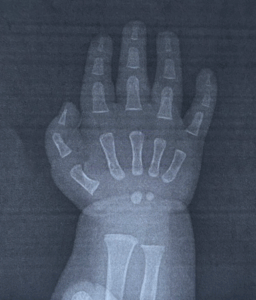

@korekieorganicさんの甥っ子くんは、今年の2月に生まれた男の子。

まだ生まれてすぐの頃にレントゲンを撮ることになり、その写真を見た瞬間、@korekieorganicさんは「小さい体でこんな経験までしちゃうんだ!」となんだか胸にぐっときたといいます。

さらに「骨って生まれたときからこんなにしっかりしてるんだ!」と感心しつつも「この小さな体で毎日頑張って成長してるんだなぁ」と思うと愛おしさが増したとも話してくれました。

また、甥っ子くんは生まれつき左手の指が1本多いという「多指症」で、多指症は珍しいとはいいますが、痛みもなく、健康に元気いっぱい育っています。